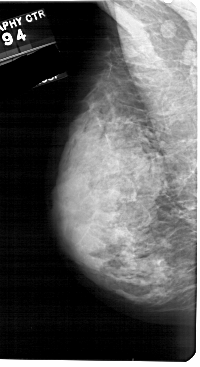

LEFT_MLO LINES 5491 PIXELS_PER_LINE 2986 BITS_PER_PIXEL 12 RESOLUTION 43.5 NON_OVERLAY